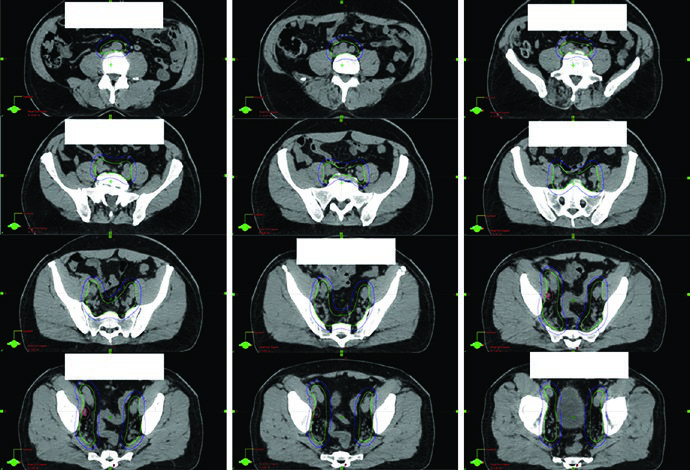

As figuras ajudam a entender por que o capítulo insiste na checagem 3D. A Fig. 25.1 mostra a sequência axial de um planejamento definitivo com TC de 2 mm fundida à RM T2, começando nas vesículas seminais e descendo até o ápice. A legenda chama atenção para o espaçador retal de hidrogel, melhor visto na RM T2, e cita o trabalho de Atluri sobre o uso de contraste iodado para facilitar a delimitação do espaçador mesmo sem apoio de RM. Já a Fig. 25.2 projeta o CTV em vistas AP, lateral e oblíquas. Ali fica claro o formato globular da glândula sob uma estrutura superior alada correspondente às vesículas seminais. Se o contorno avançar demais para o diafragma urogenital, a projeção inferior denuncia o erro rapidamente.

Outro detalhe importante da projeção tridimensional é a detecção de irregularidades slice a slice. O texto observa que correções exageradas entre cortes podem gerar um volume artificial, pouco fiel à anatomia, especialmente quando se tenta compensar deformação orgânica e movimento médio ao longo do tratamento. É um comentário curto, mas muito útil. Em próstata, boa parte dos erros não nasce de um corte catastrófico. Nasce de pequenas incoerências repetidas em muitos cortes.